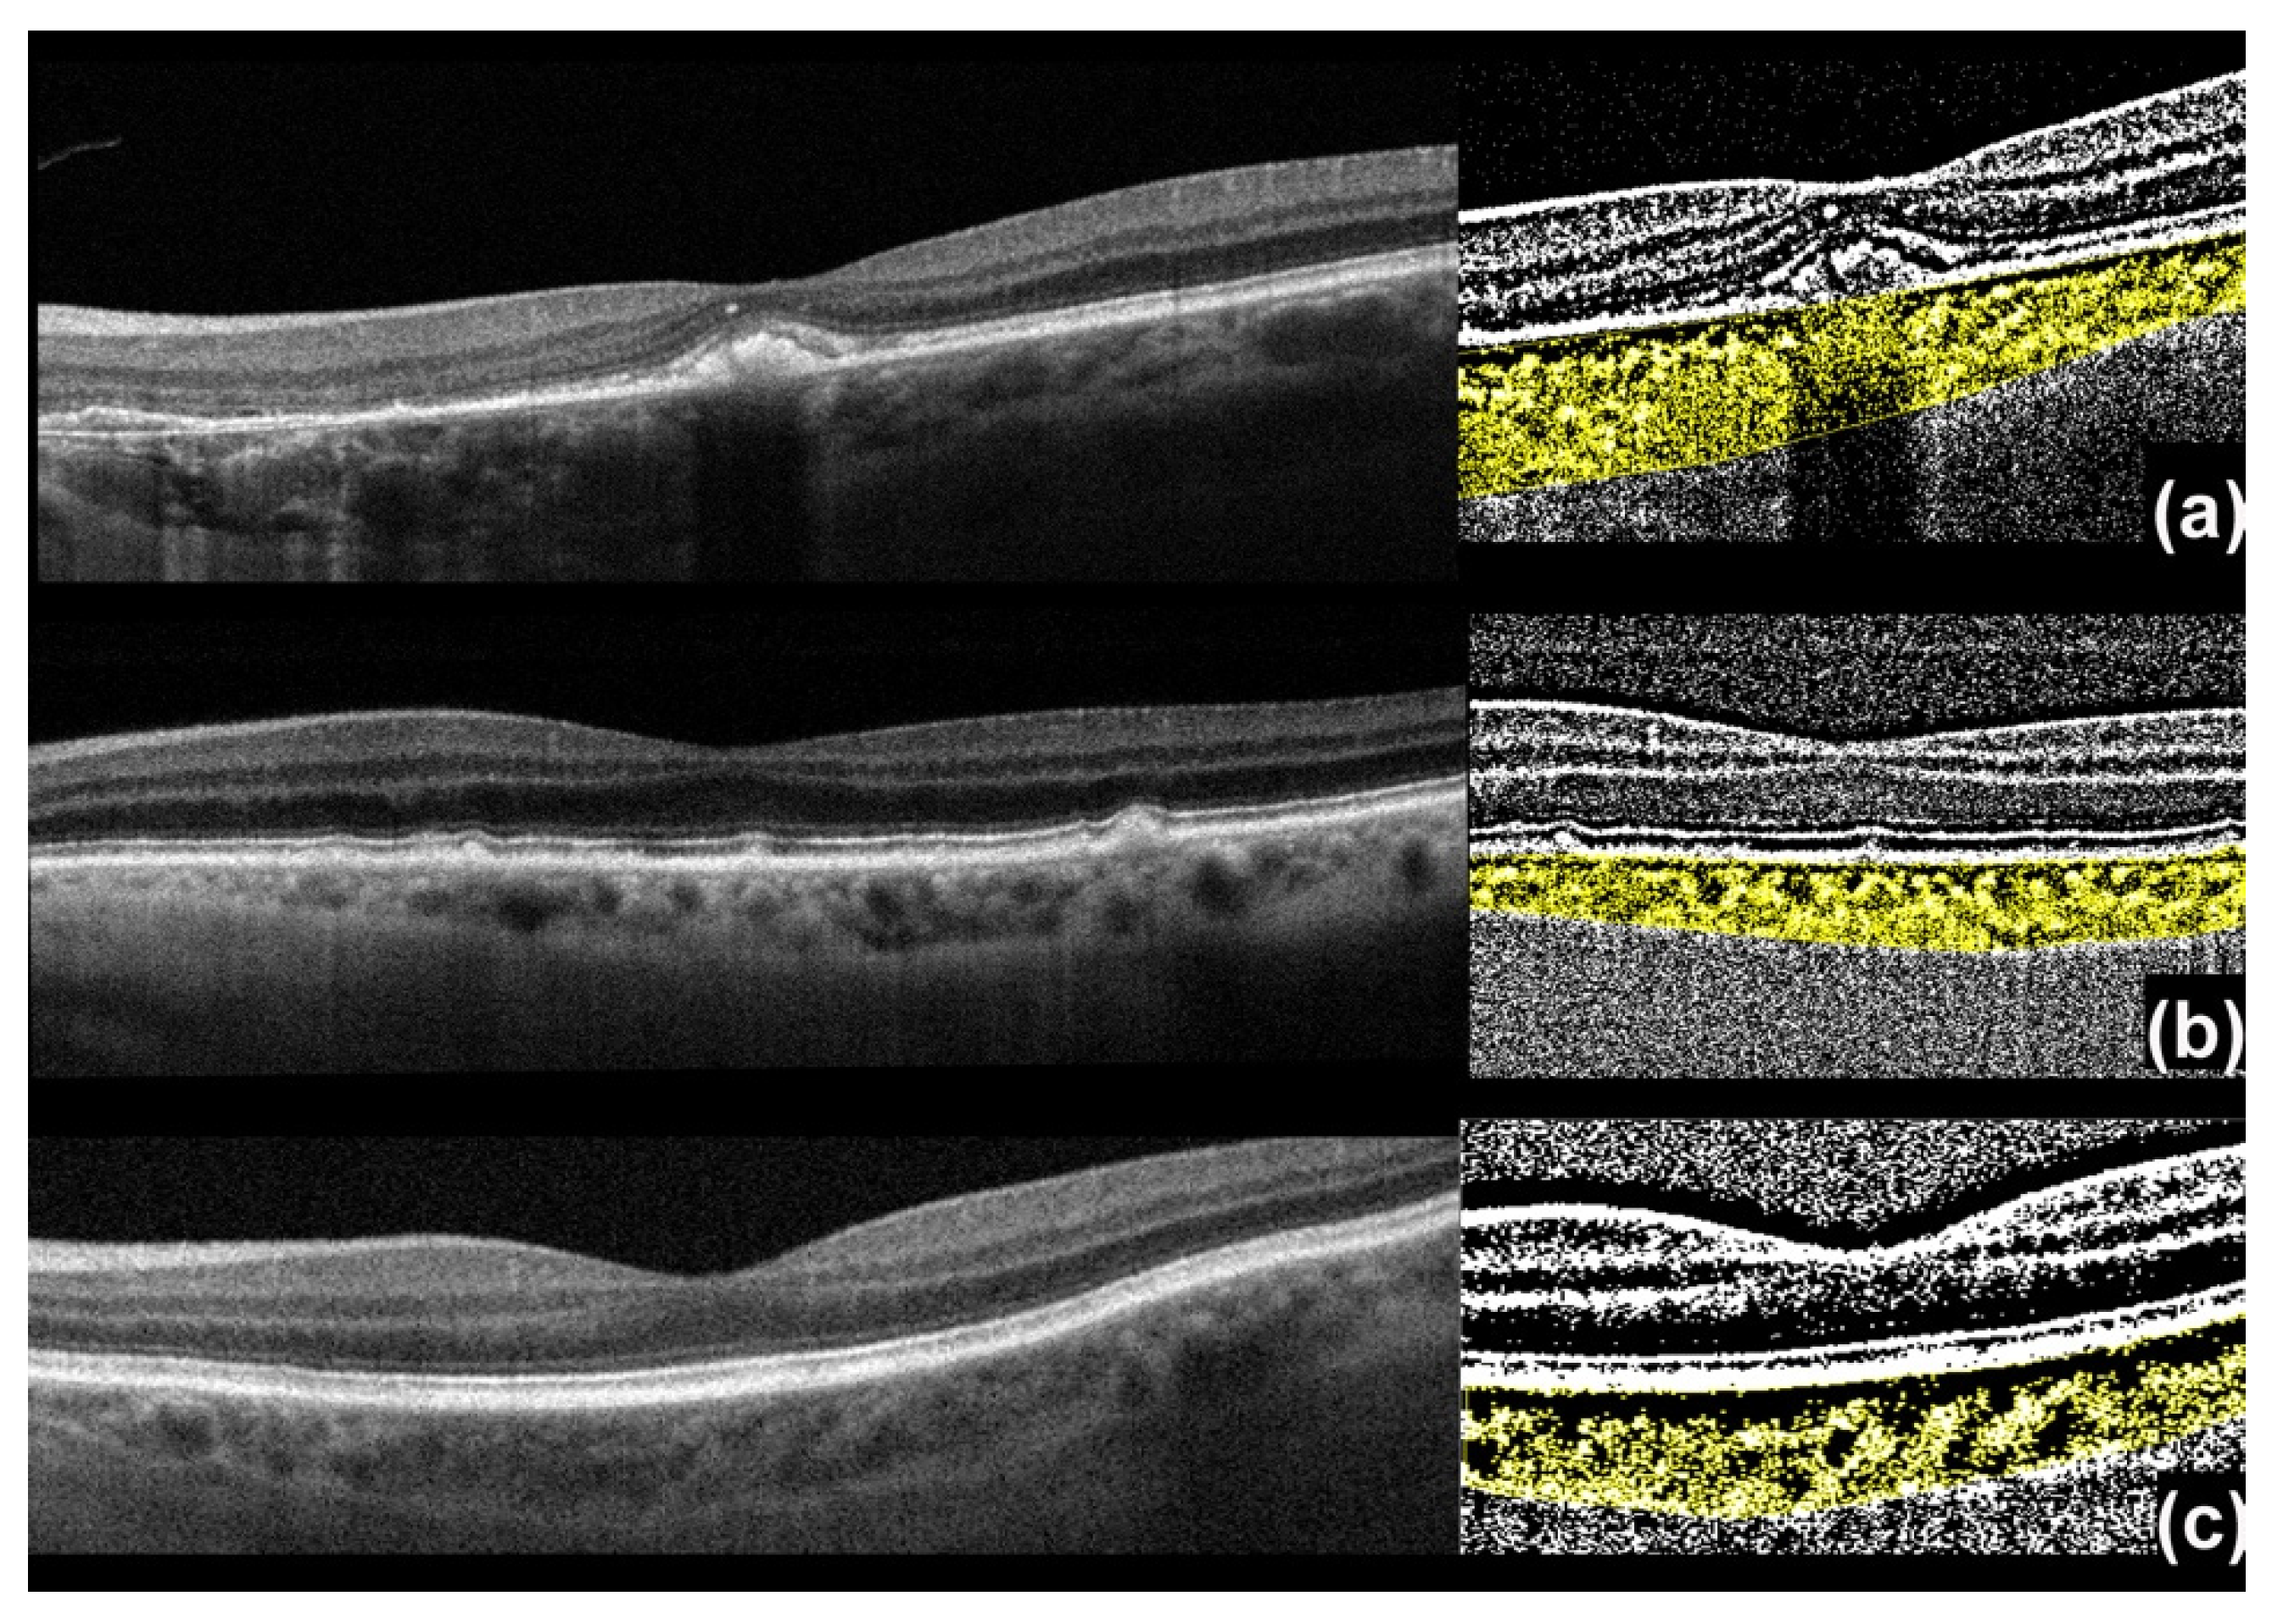

2.1. Imaging Processing

2.2. Choroidal Vascularity Index (CVI) Assessment